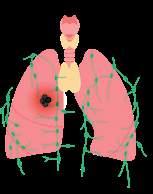

Дихальна система людини складається з дихальних шляхів: носової порожнини, носоглотки, гортані, трахеї, бронхів і легень органів газообміну між повітрям і кров’ю (мал. 16.1).

дихання. Найбільш поширеними є саме інфекційні захворювання органів дихальної системи. Їх спричинюють віруси та бактерії, які передаються переважно повітряно-крапельним шляхом. Ці збудники разом із краплинками слизу потрапляють у повітря, коли ми видихаємо, та під час чхання чи кашлю. Цей аерозоль, що містить бактерії та віруси, вдихають усі довкола (мал. 17.2). Саме тому хвора людина не має перебувати в місцях скупчення людей, особливо в

Інфекційні захворювання органів

дихання

Інфекційні запальні процеси дихальних шляхів і легень можуть спричинятися різними вірусами (аденовіруси, риновіруси та ін.) чи бактеріями (золотистий стафілокок,

дихання. Розвиток астми зумовлений спадковими особливостями імунітету людини. Проте причиною запуску алергічної реакції є фактори середовища: алергени (пил і пилові кліщі, цвілеві гриби та їхні спори), хатні тварини (шерсть, пір’я, слина), таргани, засоби побутової